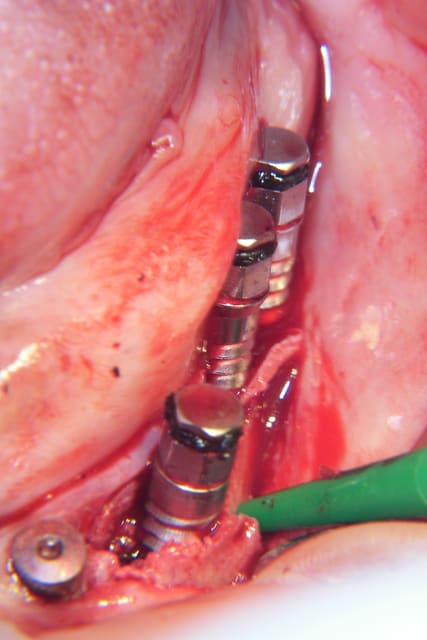

comme cela ?

photo reçue, pud de formation implanto

Exactement Ceramik .

C'est plus facile en haut qu'en bas ( os + élastique)

C'est plus facile sur de grandes étendues que sur unitaire ( + idem que pour un lambeau, meilleur lasticité)

J'utilise piezo pour la première tranchée puis ciseaux à os pour amorcer le clivage

et je termine par foret de 2 mm plus osteotome à frapper ou expanseur de Mis

Parfois un coup de foret terminal ou plus petit selon le site et le cas

Parfois décharges osseuse mesial distal et parfois ( en bas) amorce du pliage apicale

Comme dit pavx il faut prendre son temps et "sentir" l'os